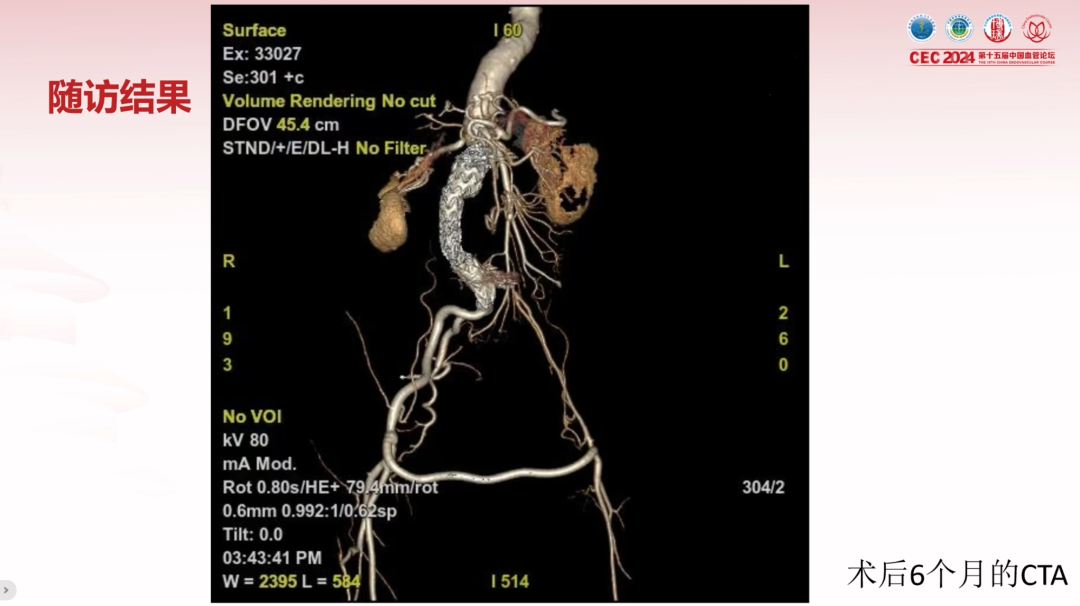

术后随访与疗效

术后患者腹部搏动性肿块消失,切口愈合良好,术后1周顺利出院。

6个月随访CTA显示动脉瘤完全封闭,无Ⅰ型、Ⅱ型内漏;右侧髂动脉及人工血管桥通畅,左侧髂内、外动脉显影正常。